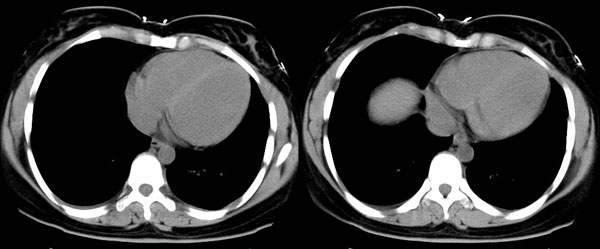

女性,25岁。反复咯血3年,再咯10天。外院x线胸片示:肺炎?支扩?

ct所见:左肺下叶基底段见大片状毛玻璃样改变,其内可见扩张细支气管。

ct诊断:考虑支气管扩张合并感染.

ct所见:左肺下叶基底段见大片状毛玻璃样改变,其内可见扩张细支气管及血管纹理影。后接正常描述。

ct诊断:左肺下叶支气管扩张伴出血。

胸部ct平扫所见:胸廓两侧欠对称,左侧略小,胸壁骨质结构完整。左肺下叶后、外基底段

见大片状毛玻璃样淡薄影,边缘渐淡,其内可见多个环形小囊状影。余肺野清晰,

肺纹理规则,气管支气管通畅,内壁光滑。心脏、大血管大小、形态、密度未见

明显异常,胸膜不厚、光滑,纵隔内未见明显肿大淋巴结。

诊断意见:左肺下叶大片状毛玻璃样淡薄影考虑支气管扩张伴出血。

我觉得是出血,感染和出血密度不点不同,请大家注意观察,发些图片上来,一起讨论